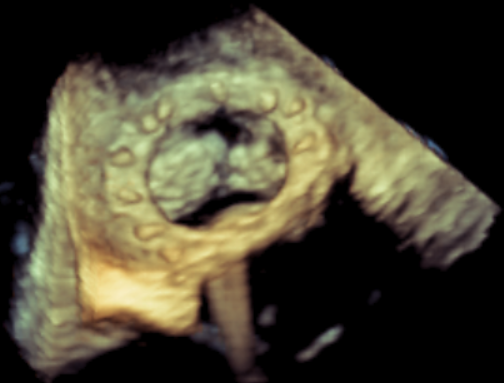

术中影像监护与评估(DSA&TEE)

CDFI提示过瓣血流通畅

CDFI示少量瓣周漏

收缩期未见瓣周漏